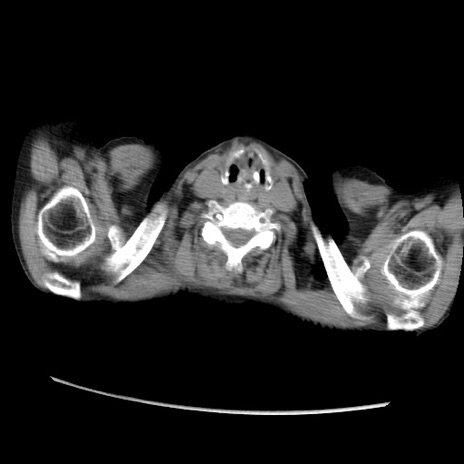

症例31(横断像)

【症例】80歳代 女性

【主訴】腹部膨満感

【現病歴】他院にて肝硬変にてフォロー中。1週間前から便秘、腹部膨満感、臍部腫瘤あり受診となる。

【既往歴】肝硬変

【身体所見】腹部膨隆あり、皮膚変化なし、疼痛なし。

【データ】WBC 4600、CRP 0.25